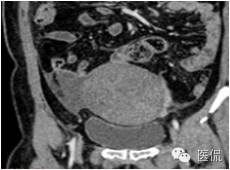

右侧卵巢肿瘤大小8*10*12cm,与膀胱后壁腹膜、盆腔侧腹膜、部分大网膜、乙状结肠直肠浆膜层前粘连,表面呈褐色坏死状,肿瘤蒂部顺时针扭转两圈,左侧卵巢正常。

◆为单发肿瘤,表现为盆腔内实性肿块,囊性区较小;境界较清楚;肿瘤体积一般较大

合并少量腹盆腔积液;有雌激素分泌增高时,合并子宫内膜增厚

◆CT表现:平扫呈等或稍低密度肿块,低于子宫肌层,可伴少量低密度囊变区,无壁结节

◆增强肿瘤实性成分呈轻-中度不均匀延迟强化,明显弱于子宫肌层;也可无强化